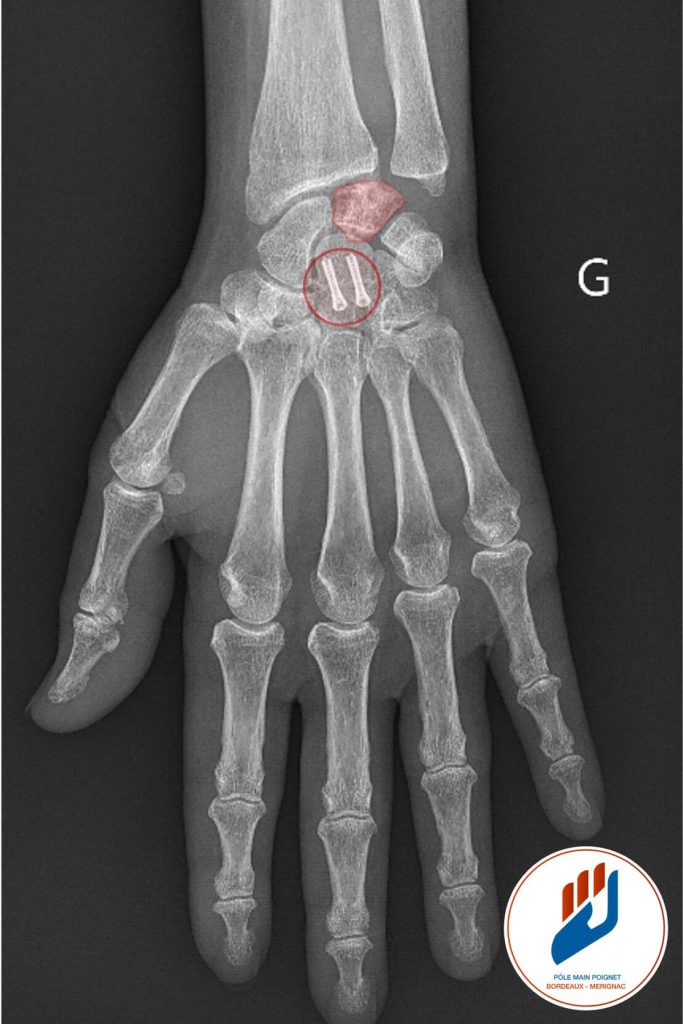

La maladie de Kienböck est une pathologie rare du poignet qui touche l’os semi-lunaire (en rouge sur la figure 1). Elle se caractérise par la nécrose du lunatum. Cette nécrose osseuse est la conséquence d’un manque de vascularisation sanguine destiné à cet os. L’os perd sa solidité et peut progressivement se fracturer. Cette maladie entraîne généralement des douleurs, des raideurs et une perte de mobilité du poignet, affectant la qualité de vie. Elle évolue vers l’arthrose du poignet.

L’imagerie joue un rôle essentiel dans le diagnostic de la maladie de Kienböck et permet de déterminer son stade. La radiographie standard reste le premier bilan à réaliser. Elle permet de voir les fractures ou la déformation du lunatum dans les formes avancées de la pathologie. Cependant, les premiers stades de la nécrose peuvent ne pas être visibles sur les radiographies classiques.

Traitement chirurgical : Remplacement prothétique du lunatum : Implant en pyrocarbone APSI

Lorsque l’os lunatum est détruit, effondré et non viable, une alternative chirurgicale consiste à le remplacer par une prothèse en pyrocarbone (APSI®). Cette option, plus récente, est proposée au Pôle Main Poignet Bordeaux Mérignac dans des cas bien sélectionnés.

Le pyrocarbone est un matériau biocompatible, dont les propriétés mécaniques se rapprochent de celles de l’os et du cartilage. L’implant a pour objectif de :

- Maintenir l’espace carpien après l’ablation du lunatum,

- Préserver une certaine mobilité du poignet, contrairement aux techniques de fusion,

- Réduire significativement les douleurs liées à l’effondrement et aux frottements osseux,

Cette technique est principalement indiquée dans les stades intermédiaires ou avancés de la maladie de Kienböck (IIIB–IV) chez des patients motivés, souhaitant conserver la mobilité de leur poignet et éviter une chirurgie plus radicale.

Le recul scientifique montre des résultats encourageants, avec une amélioration de la douleur, une conservation fonctionnelle et une satisfaction élevée des patients.